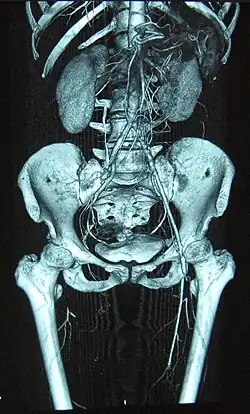

Oclusión completa de la arteria femoral derecha y estenosis de la arteria femoral izquierda como se observa en un caso de tromboangitis obliterante

La enfermedad se suele presentar sobre la tercera o cuarta década de la vida aunque durante mucho tiempo puede pasar inadvertida sin diagnóstico.[1] Afecta sobre todo a paquetes vásculo-nerviosos de sectores distales de las extremidades, pantorrilla y antebrazos, produciendo oclusiones distales y segmentarias de arterias del tobillo, pie y manos, manifestándose en forma de dolor al caminar (claudicación) por falta de llegada de sangre arterial al pie o lesiones necrosantes digitales que pueden evolucionar a la gangrena precisando amputación. Igualmente afecta a venas superficiales de tobillos y pies originando flebitis superficiales.[1]

El diagnóstico es fundamentalmente clínico y es recomendable la implicación de un especialista en enfermedades vasculares, aunque se suelen realizar estudios analíticos para descartar otro tipo de vasculitis y arteriografía si el paciente pudiera ser candidato a una eventual cirugía de revascularización (by pass), hecho poco frecuente debido a la afectación terminal de las arterias que suele imposibilitar este tipo de cirugías.[3]